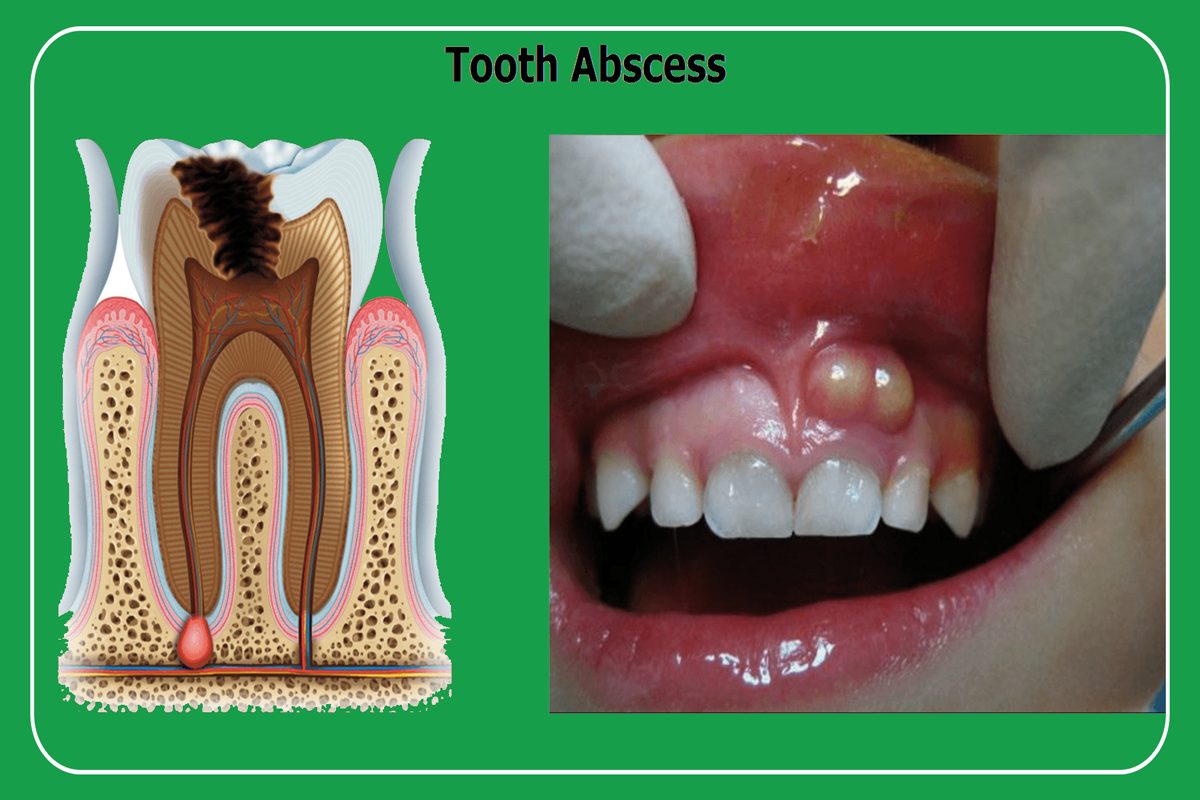

Dis Apsesi Yuz Sismesi Nasil Gecer Dis Apsesi Tedavisi

Dis Apsesi Dis Estetigi Gulus Tasarimi Dr Dt Omer Bayar

Dis Apsesi Dent Ankara

Dis Apsesi Dis Estetigi Gulus Tasarimi Dr Dt Omer Bayar

Dis Apsesi Dis Estetigi Gulus Tasarimi Dr Dt Omer Bayar

Dis Apsesi Dis Estetigi Gulus Tasarimi Dr Dt Omer Bayar